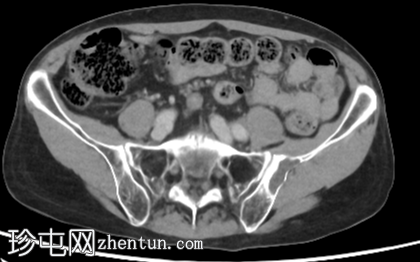

轴位骨窗

冠状位

骨窗

左侧髂骨内边界清晰的病灶

薄层硬化环

皮质变薄

轻微骨膨胀

内部密度低于肌肉和少量脂肪

薄骨间隔

无骨外软组织肿块

幸运的是,CT

影像

表现为纤维性骨发育不良,属于不可触碰的病变。